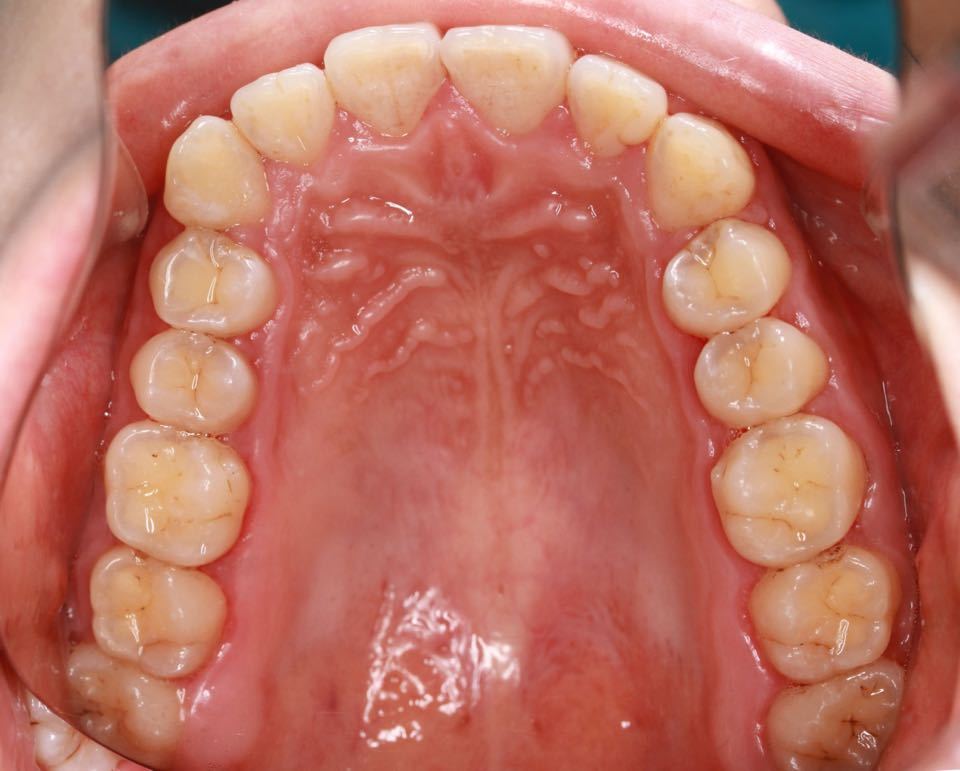

矫正前口内照:

口内:恒牙列,牙列拥挤(中度)。上下颌牙弓呈方圆型。左右对称。右侧磨牙近中性关系,左侧磨牙近中关系,右侧尖牙远中关系,左侧尖牙远牙中性关系。上颌中线偏右2mm,下中性居中。

上颌中线向患者左侧调整,上下颌中线对齐,扩弓加邻面去釉。